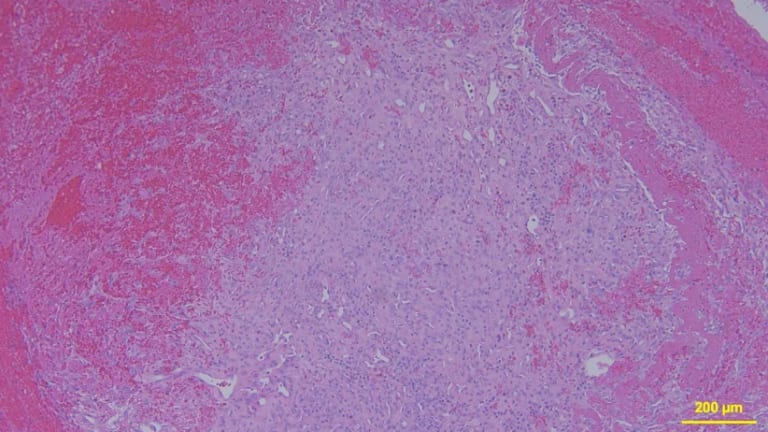

Abb. 6: Exemplarischer mikroskopischer Befund der exstirpierten Raumforderung. HE-Färbung.